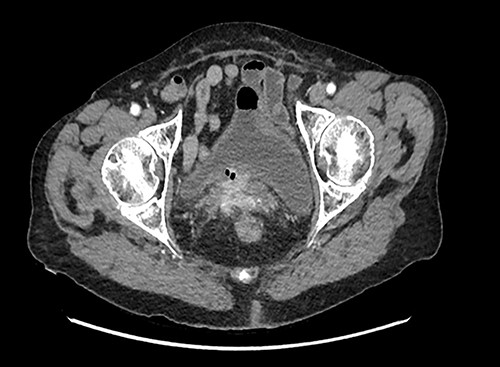

A 42-year-old woman was admitted to our unit with vaginal discharge for 1 month. She had previously undergone an open anterior mesh rectopexy for complete rectal prolapse in 1997; she also had a history of mesenteric ischemia with an extensive intestinal resection in 2005. Vaginal examination showed the polypropylene mesh protruding out through the bottom of the vagina. Digital rectal examination was normal. CT scan showed an infection with an abscess of the rectopexy mesh, inflammation and infiltration next to the lower rectum and the anorectal junction fusing into the right ischioanal fossa. It also showed a vaginal fistula at the level of the posterior vaginal fornix, with an exposure of the mesh at this level. Under general anesthesia in gynecologic position, a sub-total removal of the mesh was done using a transvaginal approach. The postoperative outcomes were uneventful.